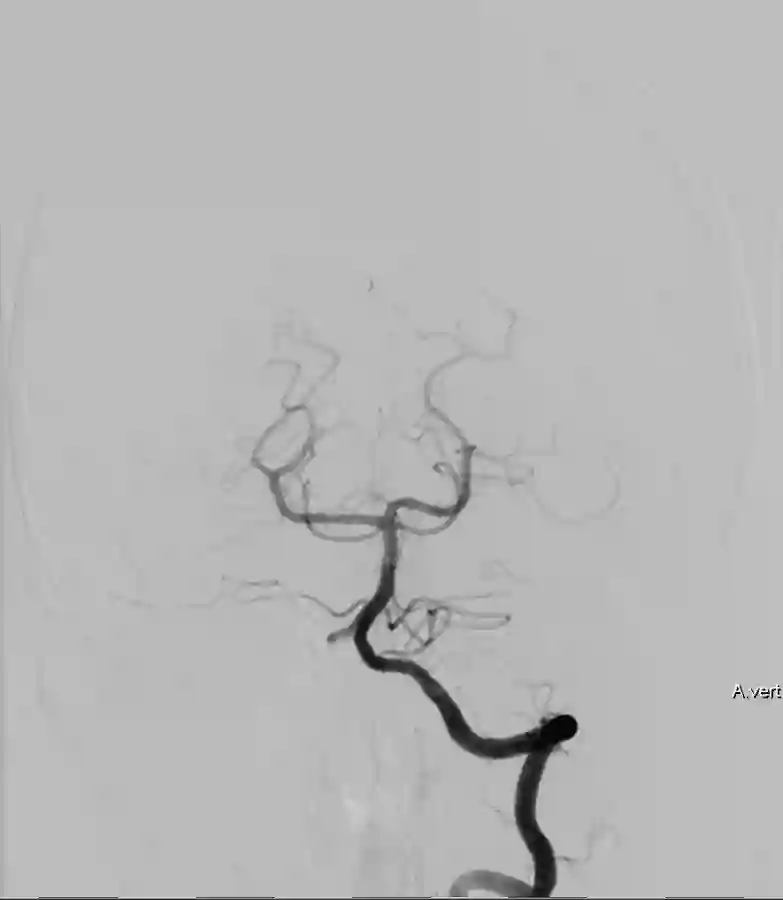

Der Goldstandard zur optimalen Darstellung der Arteria vertebralis ist die digitale Subtraktionsangiographie, kann jedoch je nach klinischer Fragestellung auch in der CT-Angiographie oder MRT Bildgebung dargestellt wird.

Im Bereich der Arteria vertebralis können typischerweise Dissektionsaneurysmen auftreten und eine Subarachnoidalblutung verursachen[^3]. Die Behandlung dieser Dissektionsaneurysmen kann je nach Fall beispielsweise endovaskuläre mithilfe von Implantation eines Flow-Diverters behandelt werden[^4] [^5].